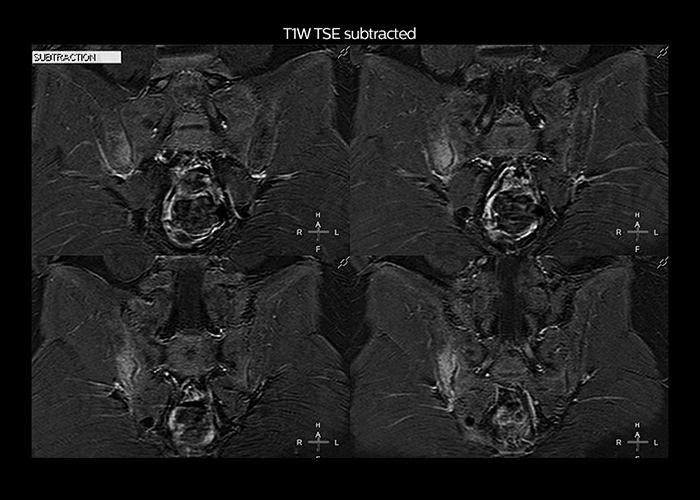

“On average, we scan about 80 patients per day, but on some days we scan well over 100 patients. The scanner is in use 7 days per week, operated 20 hours per day on week days and 8 hours per day in the weekend,” Mr. Tuna says. “To avoid coil changes we plan examinations of similar anatomies back to back, such as head and spine. Multiva helps us here a lot because coils don’t need to be changed frequently. Moreover, thanks to parallel imaging technology and 16-channel HeadSpineTorso and 8-channel MSK coils we are able to achieve excellent image quality. In this way Multiva helped us to increase both image quality and productivity.” “Neurological cases, such as brain and spine imaging, represent the largest share in our MR scanning, followed by musculoskeletal cases. In general, we use simple and basic imaging protocols. But occasionally, we use advanced techniques for problematic cases if necessary.